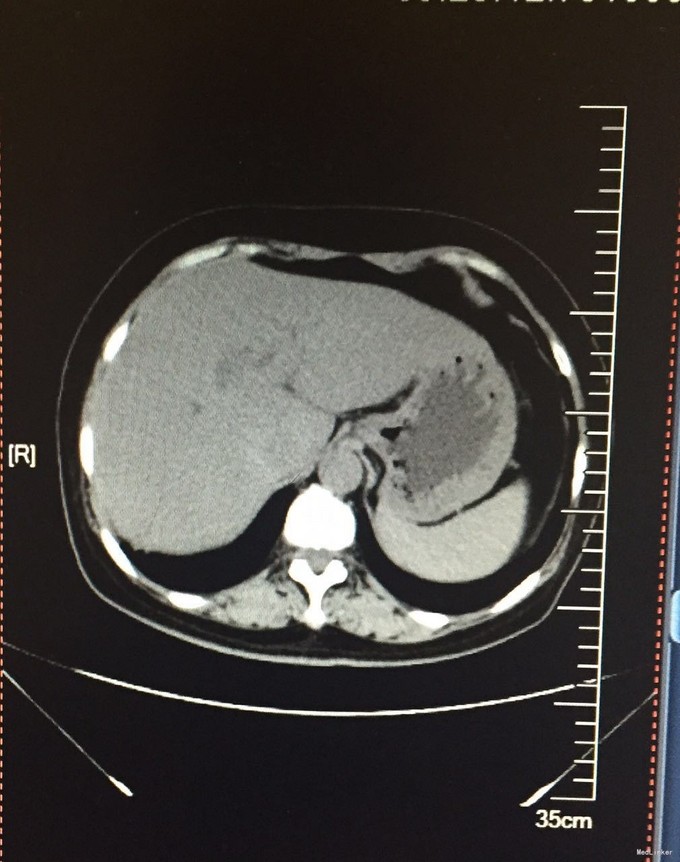

患者 57岁一月前因感冒发烧入院,当地医院给予抗炎治疗,症状未减轻,就诊于我院。

CT示:右肺下叶条索、结节影;右侧胸膜肥厚粘连,钙化,纵膈内多发小淋巴结影。2.肝左叶内侧段近肝门处稍低密度影。行右肺下叶肿瘤楔形切除术,手中可见右肺上叶,中肺表面可触及白色点状结节。右肺下叶近外周处可扪及大小约2*2*1cm的肿块,牵拉表面肺组织呈凹陷状。

术中冰冻为:“右肺腺癌,胸膜内癌转移。”术中考虑分期为T4NxM1IV期。考虑为根治手术禁忌症。遂经家属同意,制定术后化疗方案后实行化疗。最终诊断为:右肺癌(T4NxM1,IV期)